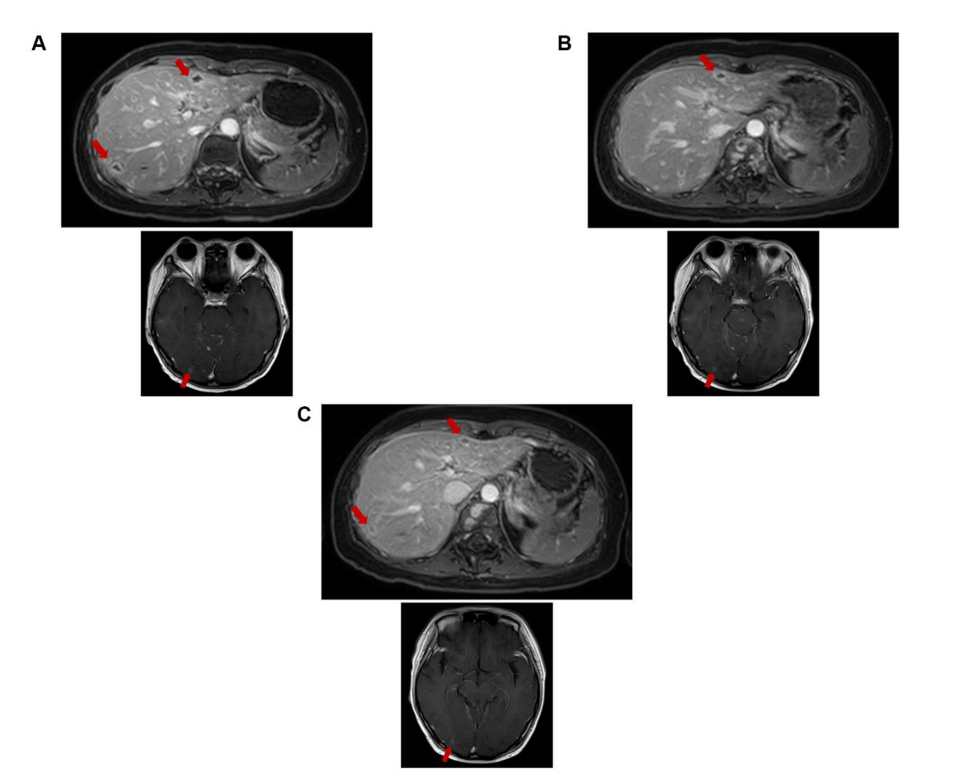

与2020年5月6日(治疗前)的MRI图像相比(图1A),2020年8月3日(4个疗程后)的MRI显示颅内(最大位于右枕叶,8-6 mm)、脑膜、颈胸腰段椎体脊髓膜、脊髓和肝多发转移灶(最大位于S3,12-9 mm)减少(图1C),肝内转移灶则在2020年6月17日(2个疗程后)肝内转移灶较MRI缩小(图1B)。

图1. 脑和肝脏的MRI图像。(A)2020年5月6日MRI(DS-8201治疗前)。(B)2020年6月17日MRI(2个疗程后)。(C)2020年8月3日MRI(4个疗程后)。